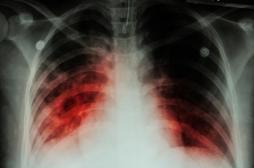

LES MALADIES

SYMPTÔMES